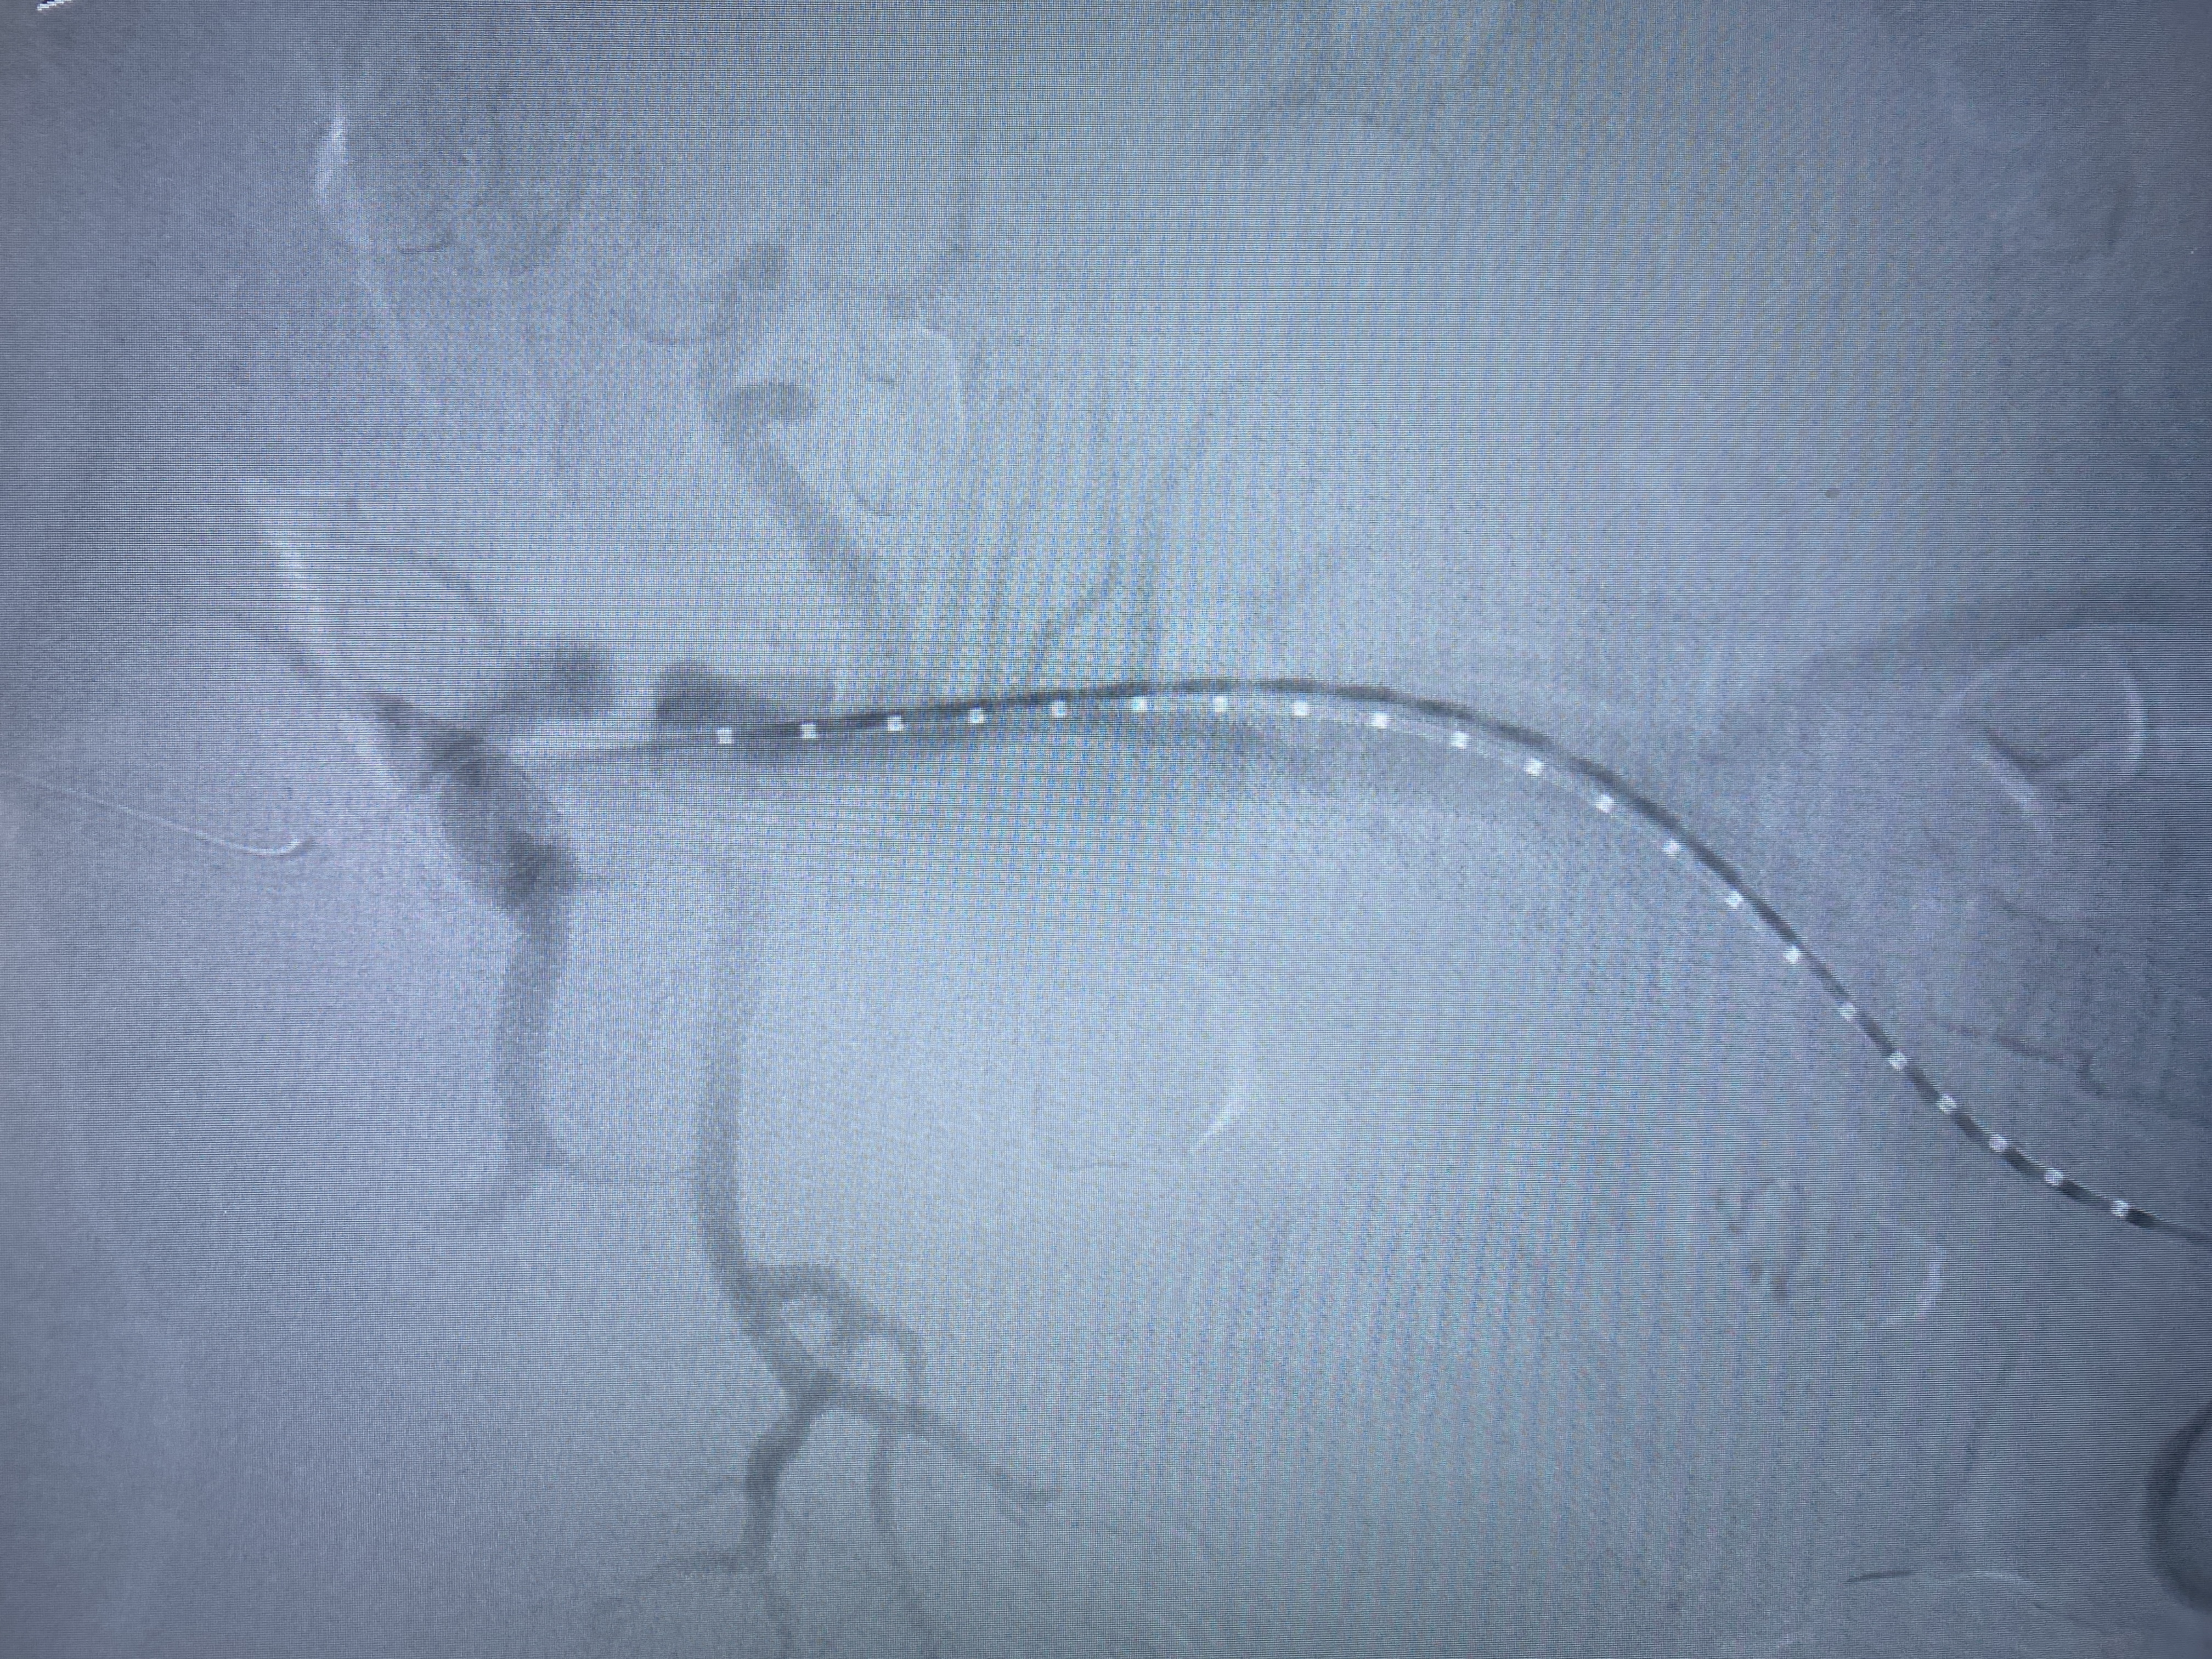

由于患者手术情况复杂,血管外科团队与介入导管室、麻醉科等积极沟通并进行充分的手术准备,在多学科相互配合下,为患者行腹主动脉覆膜支架置入及“四开窗”术,手术顺利,完美隔绝夹层破口,保留腹腔干、肠系膜上动脉、双肾动脉,患者恢复良好。

据市第二人民医院血管外科主任、副主任医师、阜阳市医学会外科学分会血管外科学组组长、血管外科学科带头人芮清峰介绍,累及内脏动脉的主动脉瘤或主动脉夹层一直是治疗的难点,传统外科开放手术,创伤大、并发症多、死亡率高。随着微创技术的发展,主动脉腔内修复已成为主动脉疾病的主流治疗方式,微创、并发症少;但是累及内脏动脉的纯腔内治疗(开窗支架或分支支架技术)操作复杂,依照分支血管位置,在支架上开出对应的"窗口",个体化设计支架,在隔绝主动脉瘤或夹层的同时,避免了分支血管缺血。应用开窗型带膜支架,术中使支架上的孔道与分支血管相对,既能避免封堵重要血管,又可获得足够的封堵区域。